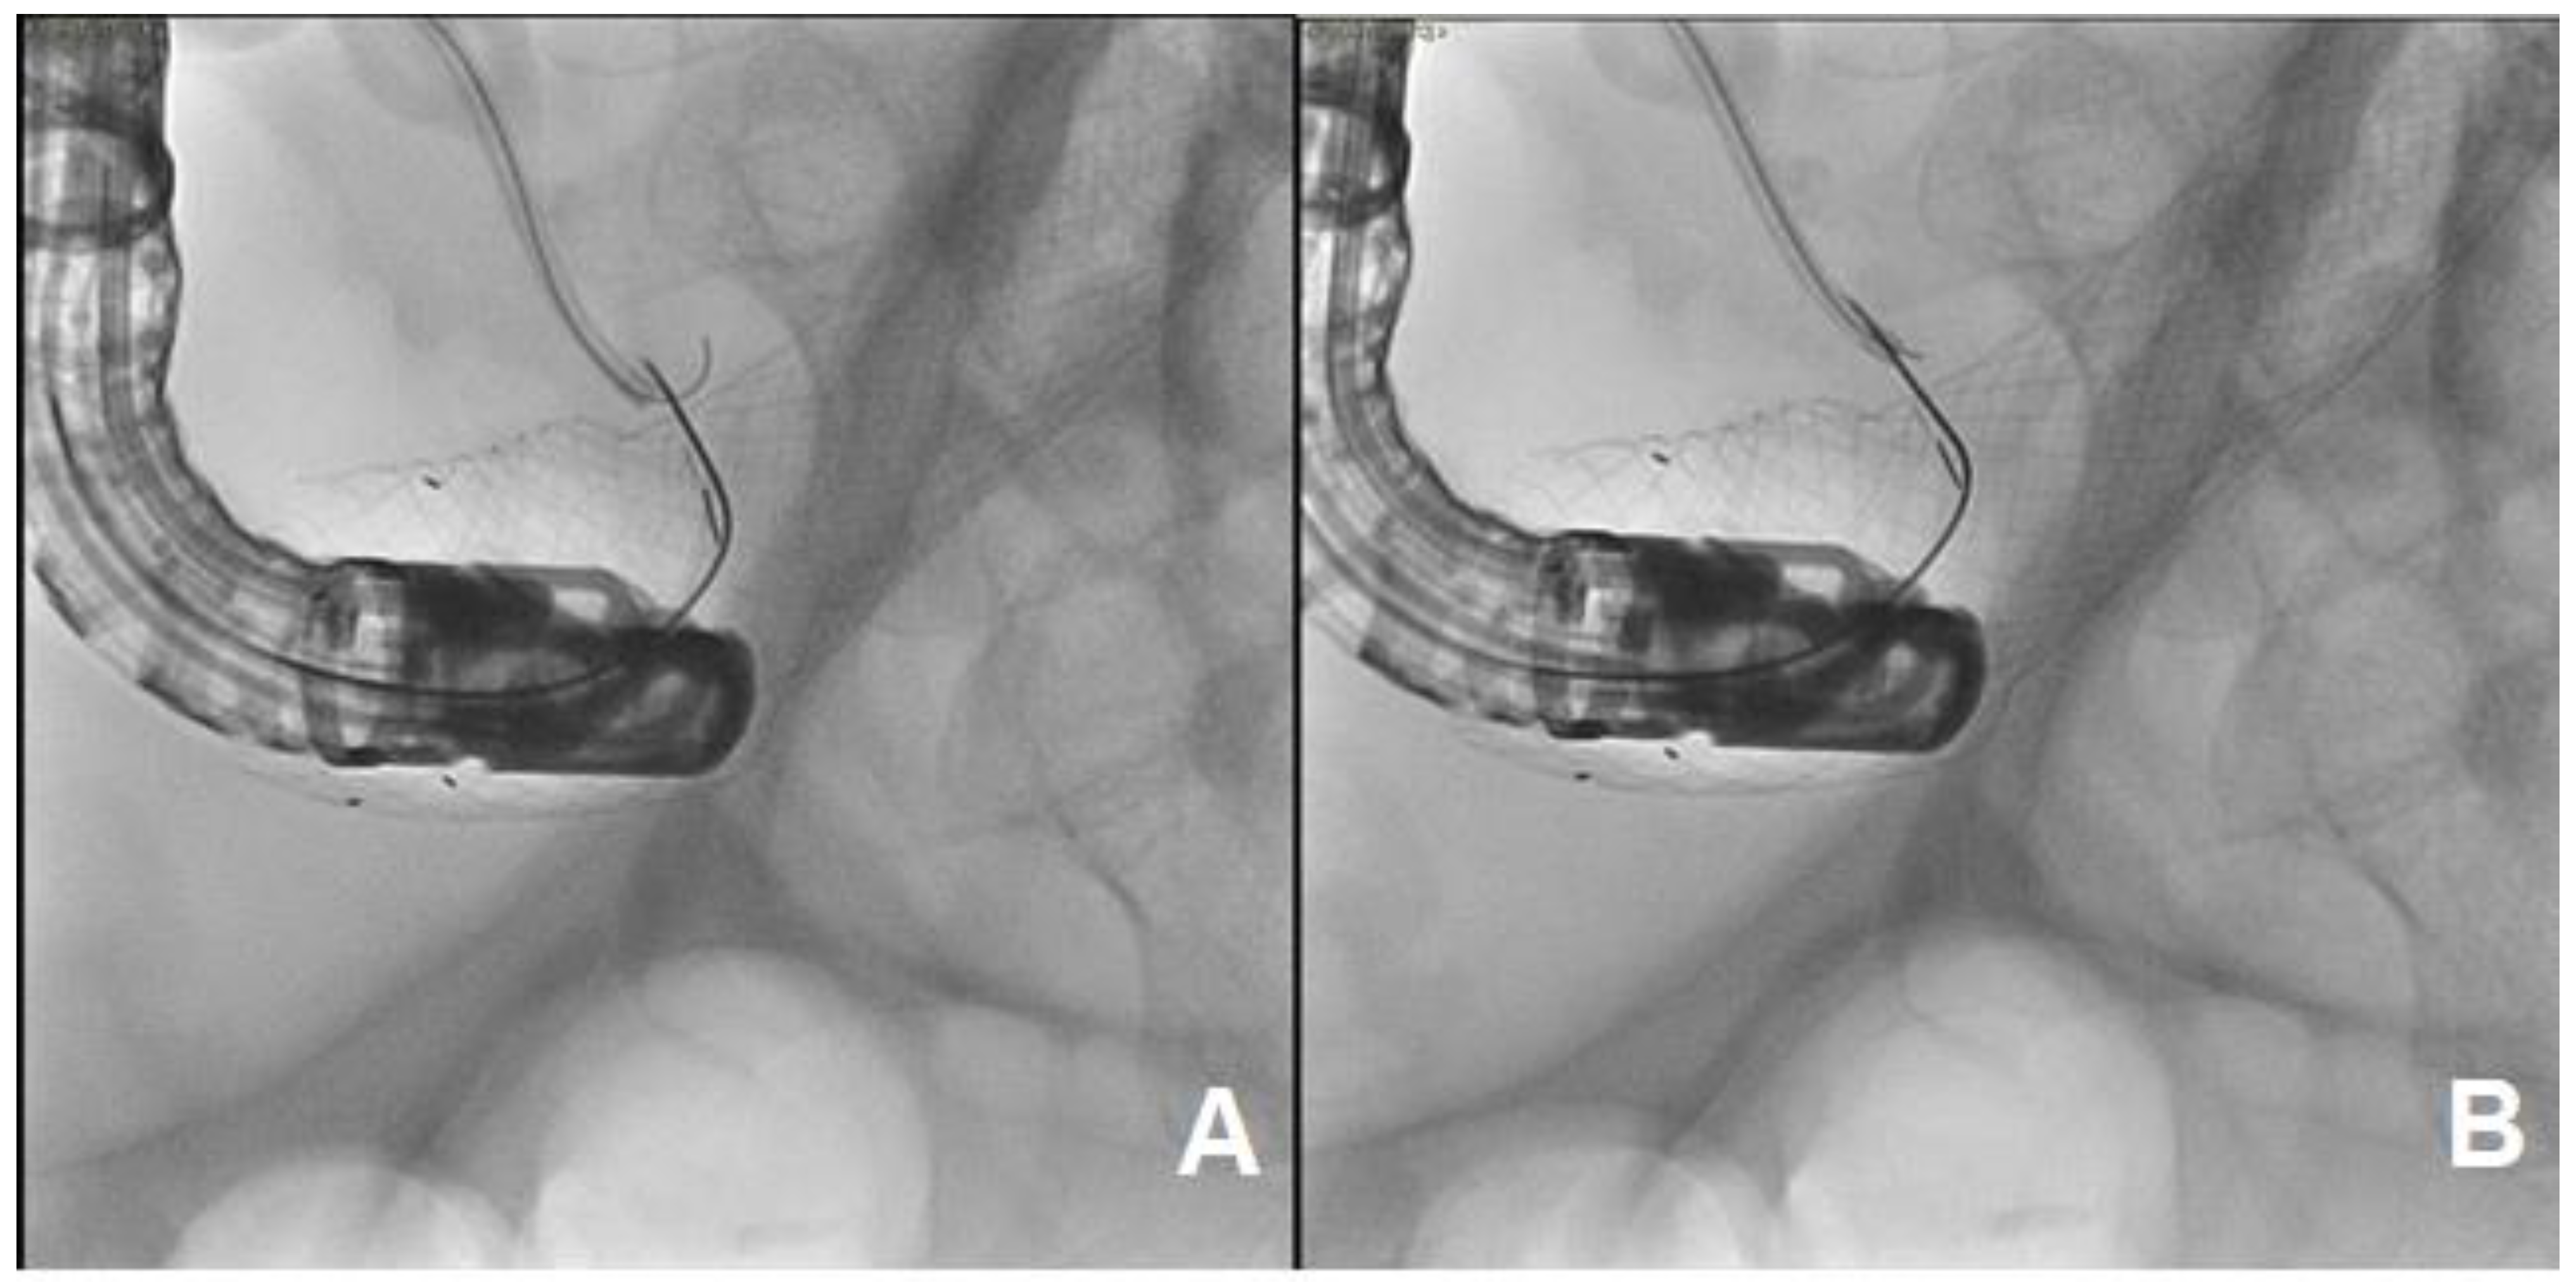

2. Case Discussion